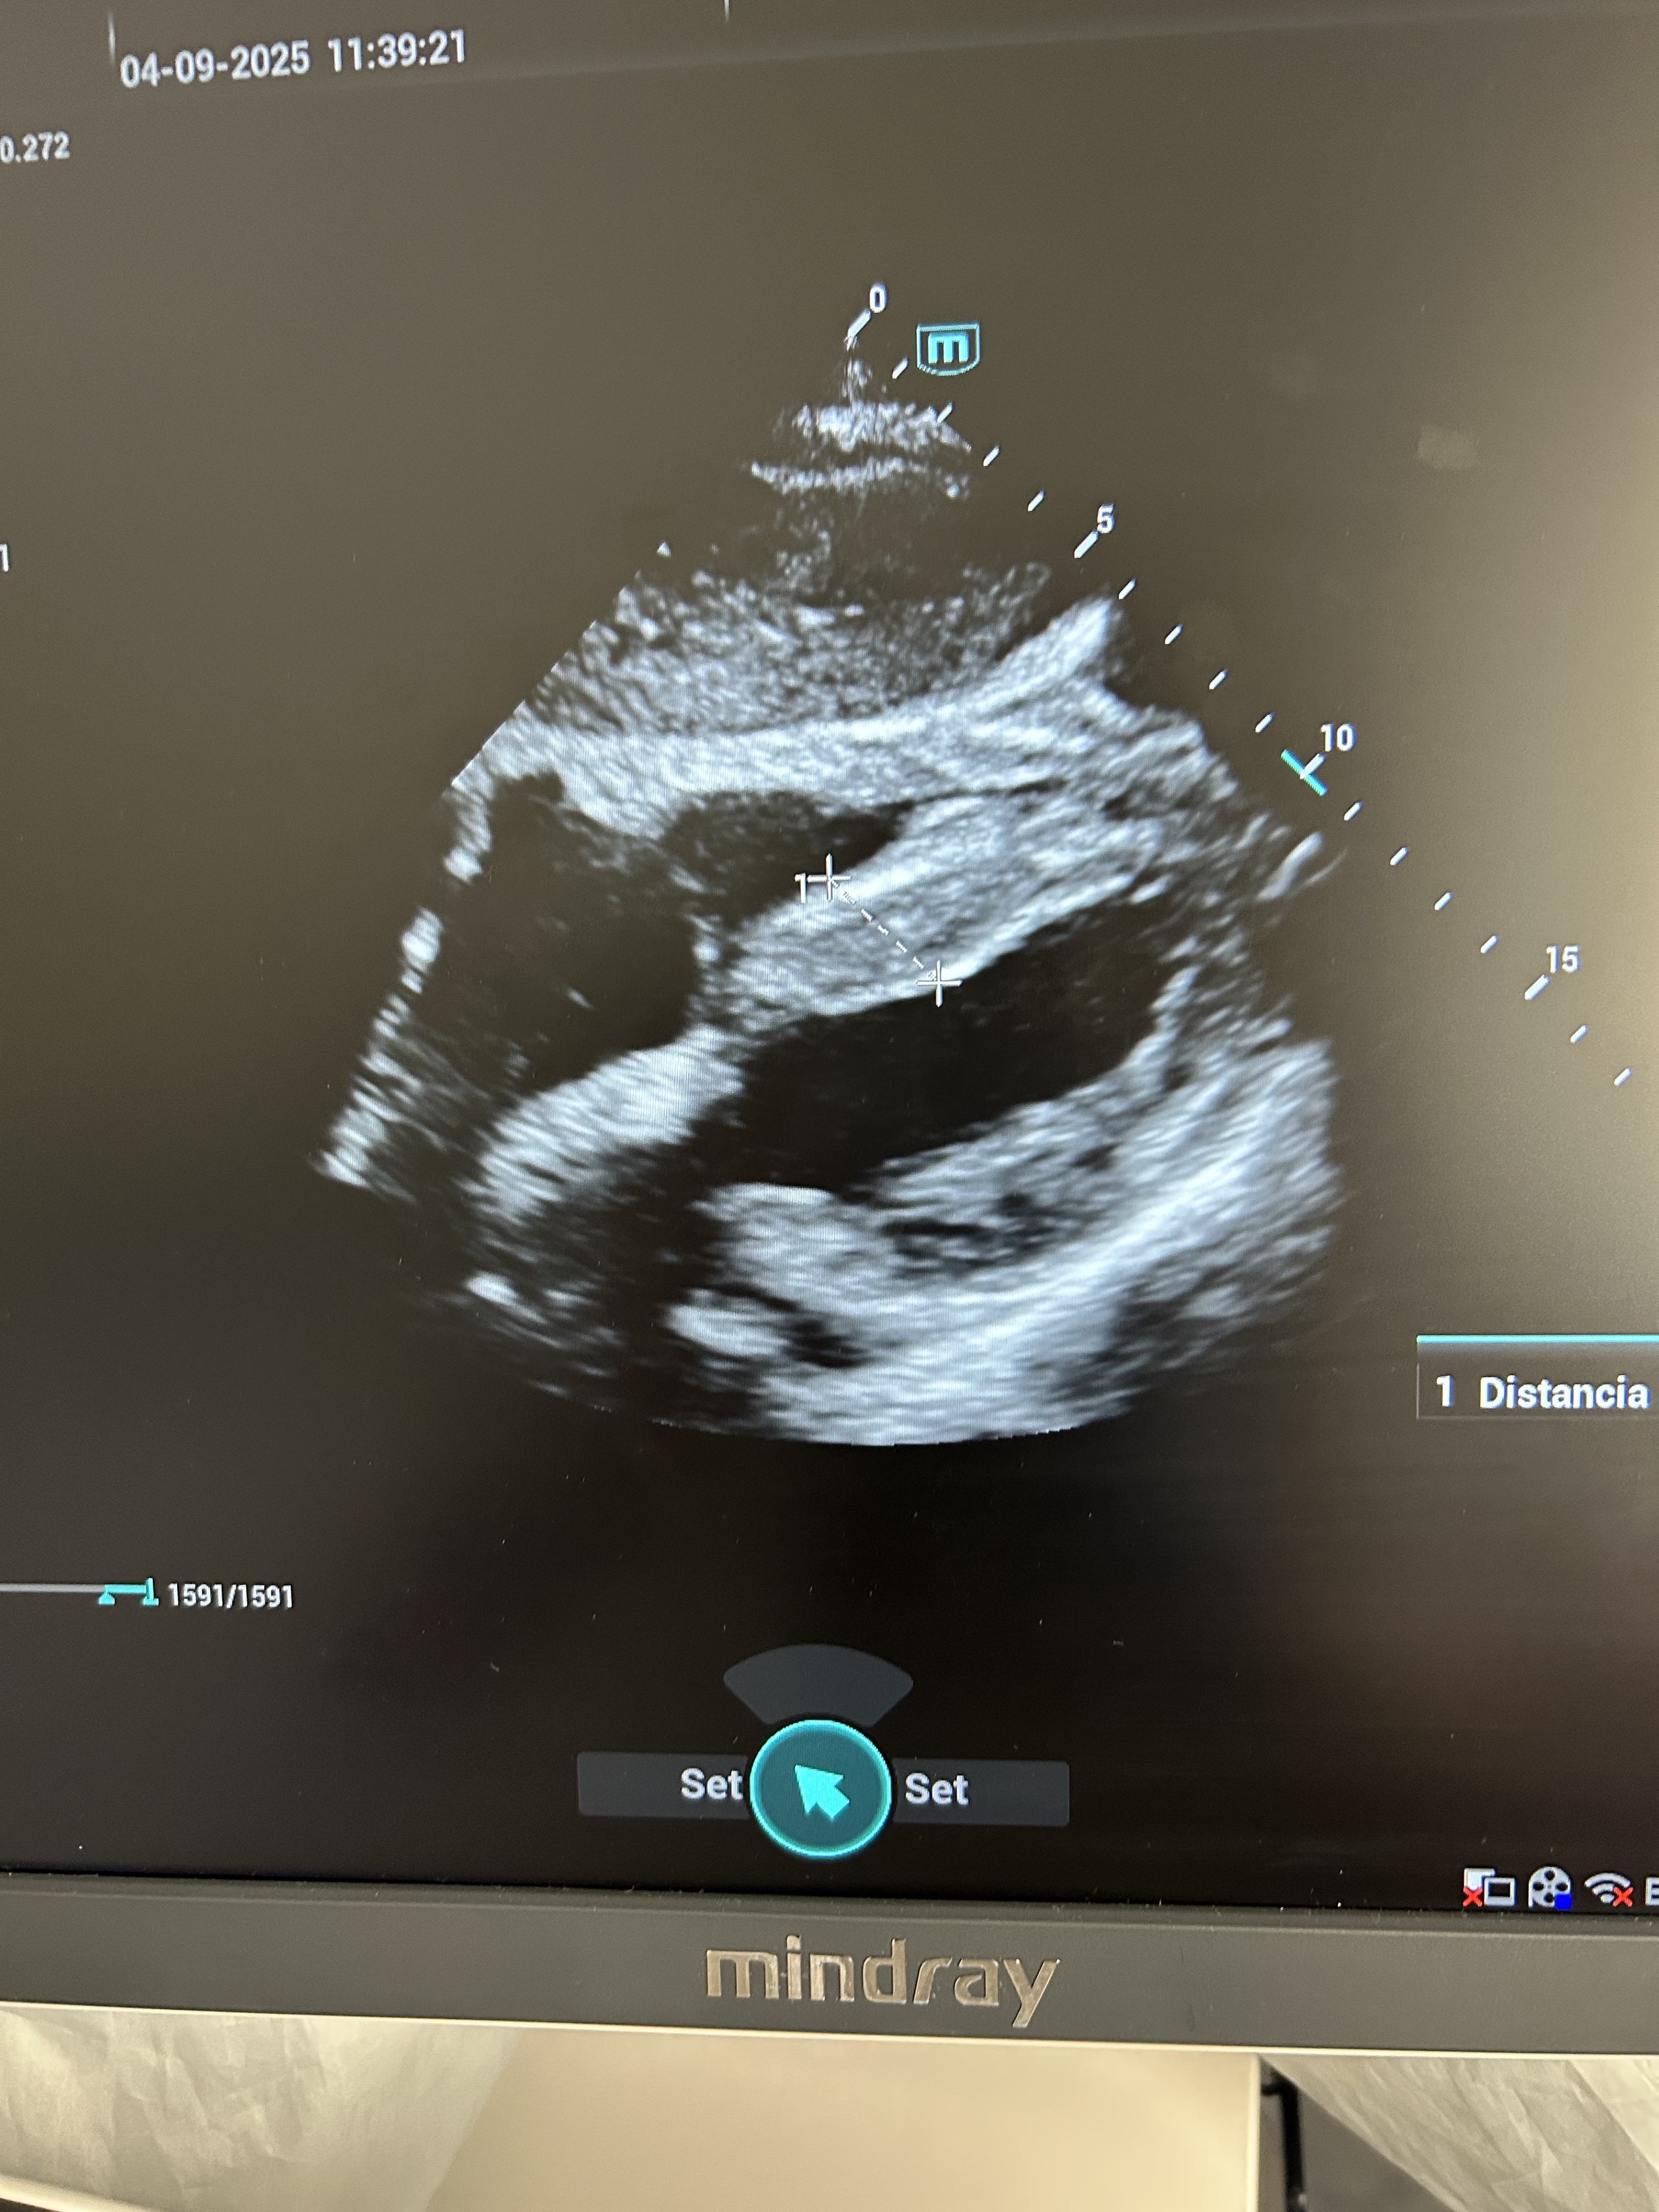

Hallazgos ecográficos

Al tratarse de un paciente con factores de riesgo cardiovascular decidimos realizar ecografía cardíaca; en la cual se visualiza una FEVI aparentemente preservada. Hipertrofia del septo con colapso de ventriculo derecho, bastante llamativa en una ventana de cuatro cámaras.